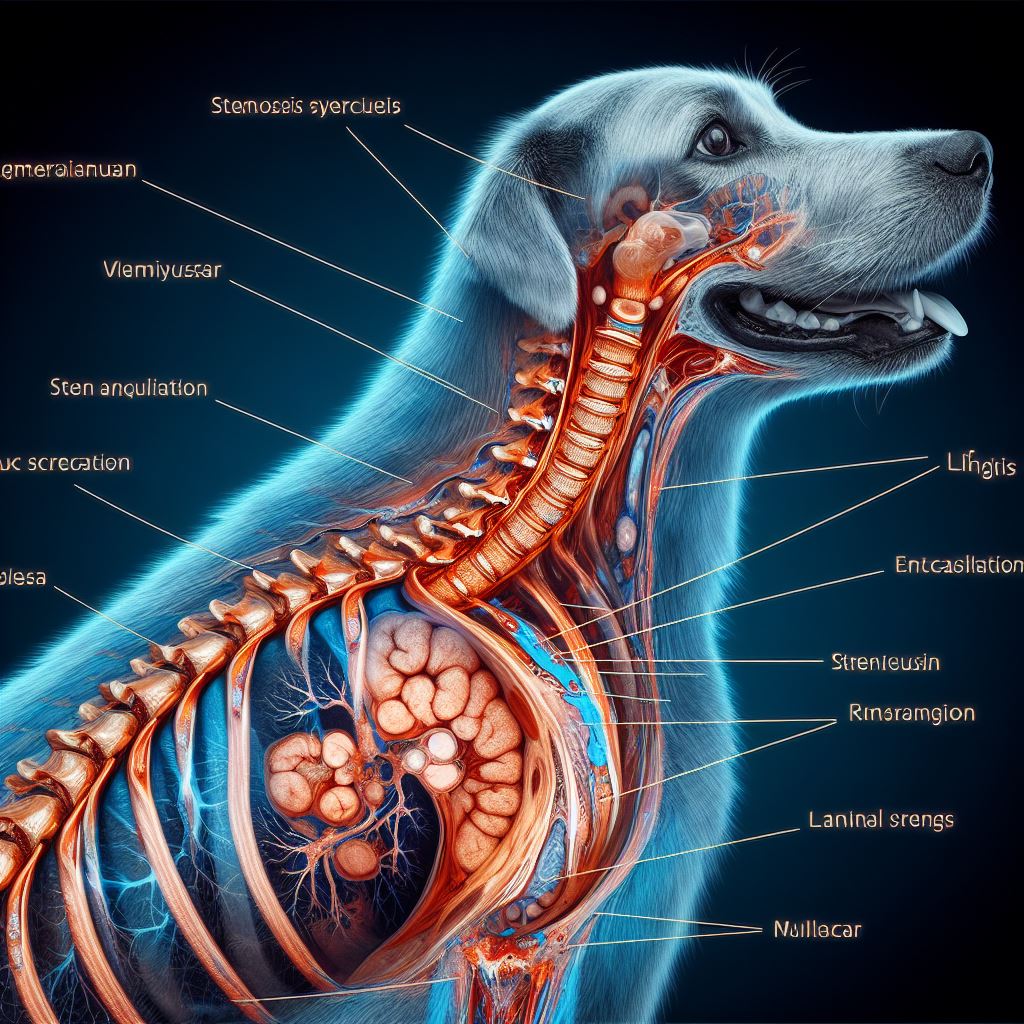

강아지 기관지 협착증 원인과 증상, 치료 방법 알아보기 사진